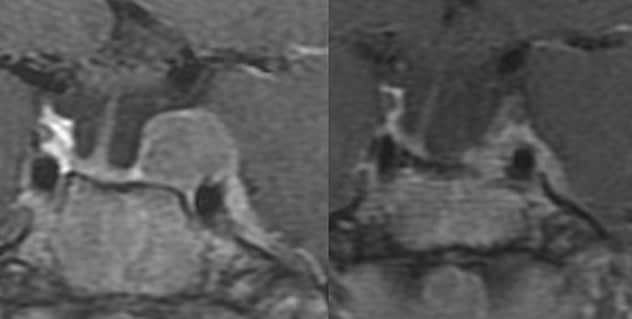

التصوير بالرنين المغناطيسي على المستوى الإكليلي لامرأة تبلغ من العمر 19 عامًا مصابة بدرجة شديدة من داء كوشينغ بعد الخضوع لجراحتين بطريق الوتدي. وخضعت المريضة لجراحة استئصال الكظر بالجانبين والجراحة الإشعاعية التجسيمية. الجانب الأيسر: التصوير بالرنين المغناطيسي السابق للجراحة الإشعاعية التجسيمية (الجرعة الحدية، 25 غراي). الجانب الأيمن: يُظهر التصوير بالرنين المغناطيسي بعد أربع سنوات من استئصال الكظر بالجانبين والجراحة الإشعاعية التجسيمية انخفاضًا كبيرًا في حجم الورم.